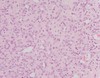

Pretibial myxedema histology

Increased mucin within the upper dermis that separates collagen bundles.

The overlying epidermis may demonstrate acanthosis, papillomatosis, and hyperkeratosis.